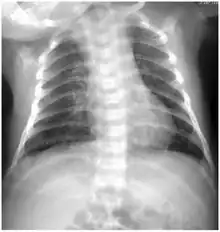

![]() | |

| Pap smear showing C. trachomatis (H&E stain) | |